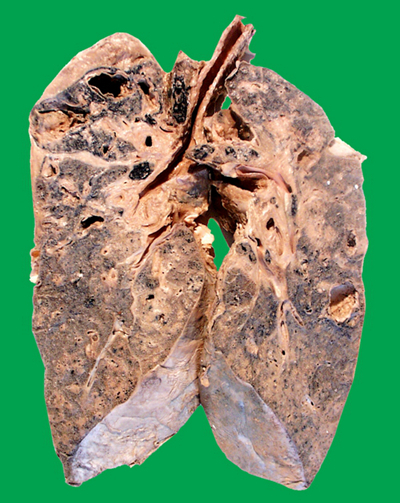

肺結核圖片

A:空洞型肺結核是指病灶中有空洞的肺結核,同樣屬於繼發性肺結核。治療的方法通常依據是初治空洞型肺結核,還是慢性纖維空洞型肺結核,併兼顧患者的臨床症狀與體徵,是否有咯血、混合感染、支氣管播散,或者肺組織受到破壞、毀損等嚴重程度,治療方法不完全相同……